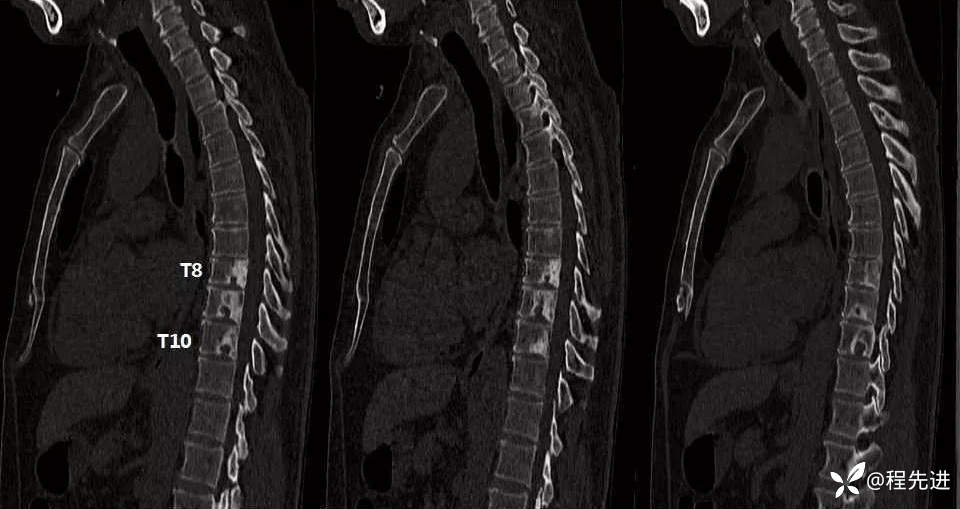

平扫骨窗

平扫骨窗矢状位